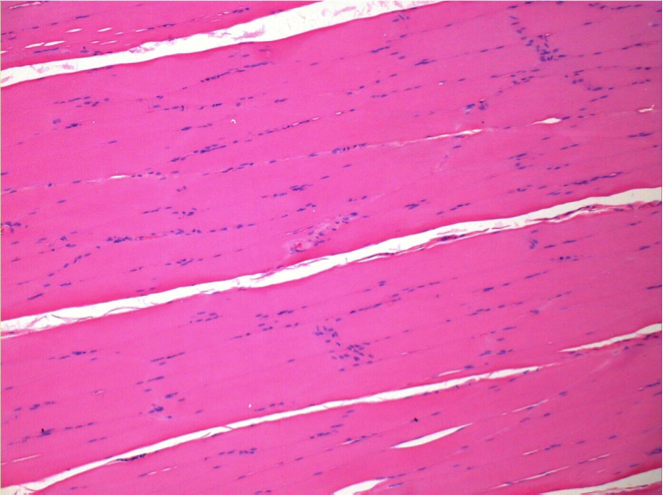

7 meses después de la inyección de Endopeel

7 meses (D210) después de la inyección IM de Endopeel 0,1 ml en el músculo pretibial derecho.

Restitutio ad integrum (restauración a la condición original) completa después de 7 meses

L : Control-100xD210

R:100xD210

L :Control 50xD210

R50X-D210